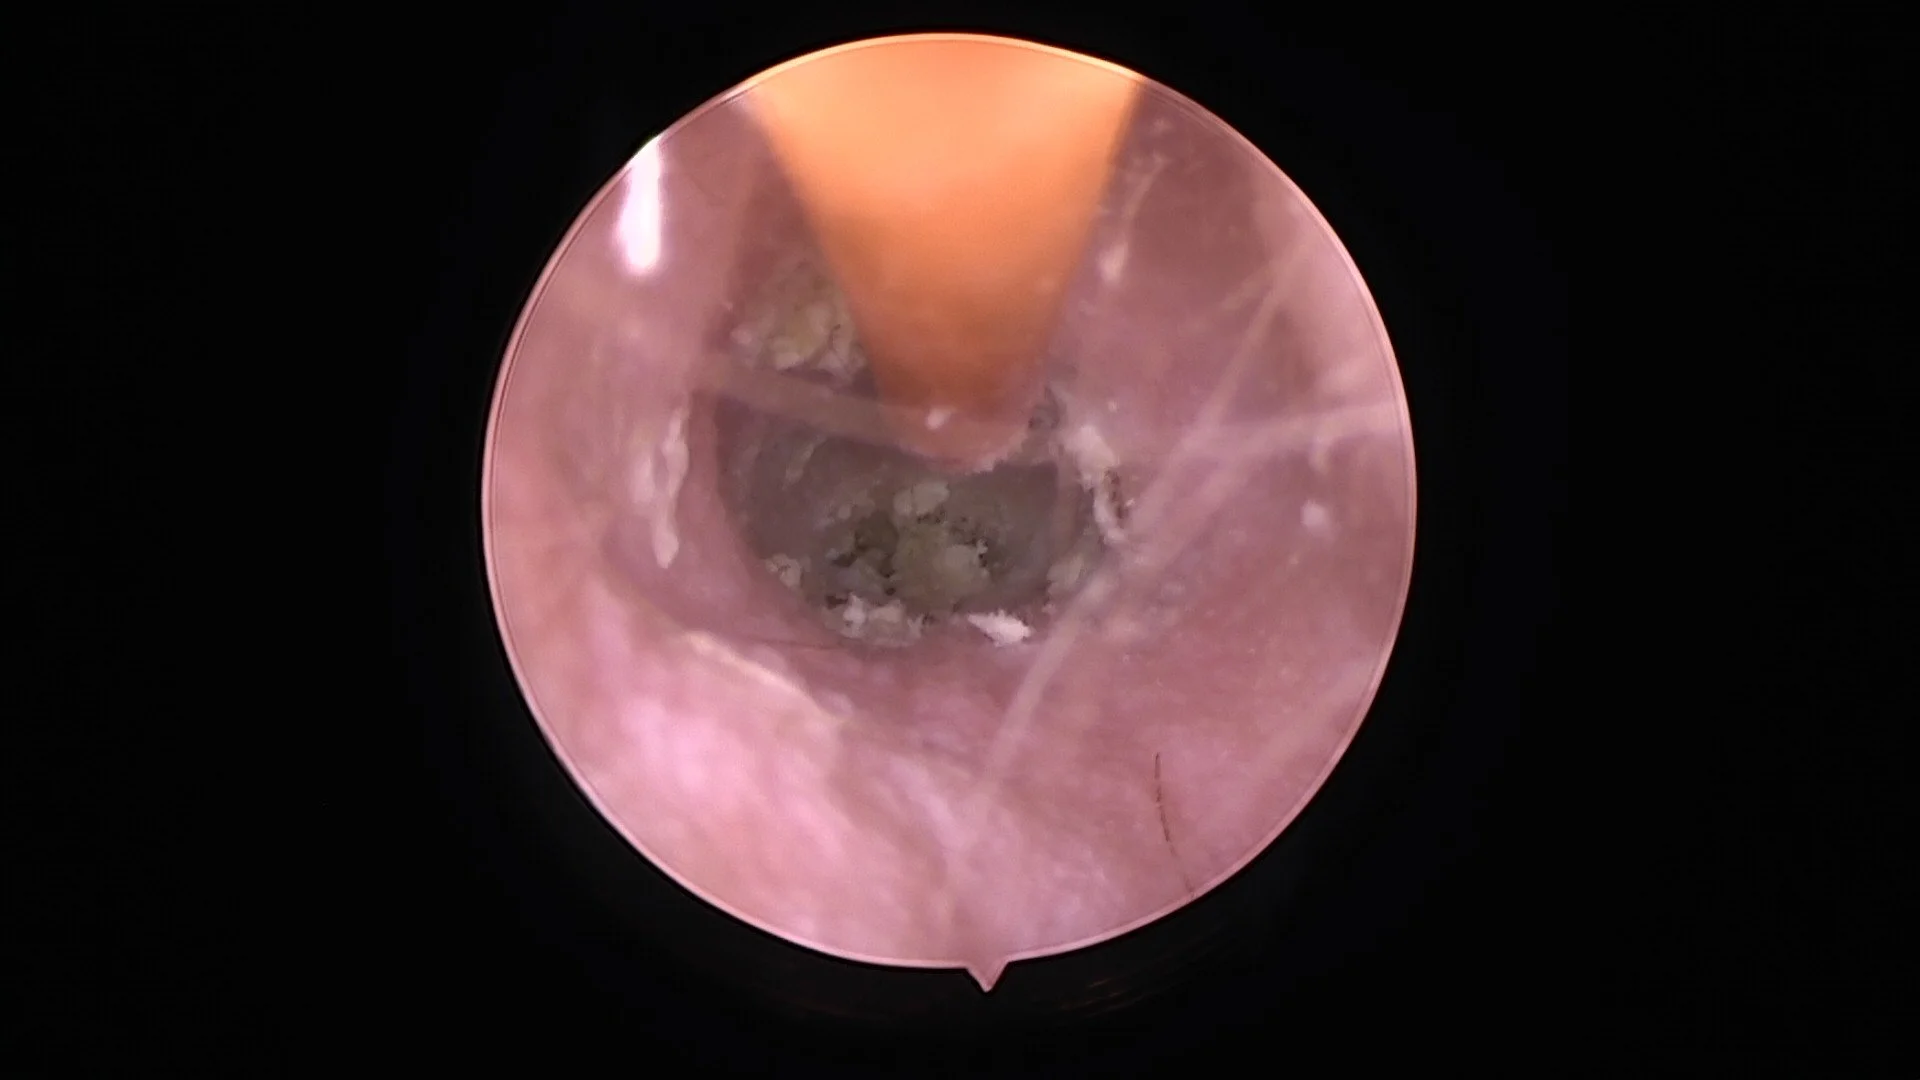

Flushing an ear canal clean with a soft catheter via our video-otoscope.

Often the first step towards resolution of chronic otitis externa is a thorough ear examination and deep ear clean under anaesthesia via video-otoscope. If there is significant canal stenosis, oral steroid medication is often prescribed for 1- 2 weeks to open up the ear canal prior to video-otoscopy.

Visualising and cleaning the ear canal with the video-otoscope increases the likelihood of identifying any underlying problem, or deeper complications such as ruptured tympanic membranes, otitis media, foreign bodies, ear canal masses or inflammatory polyps.